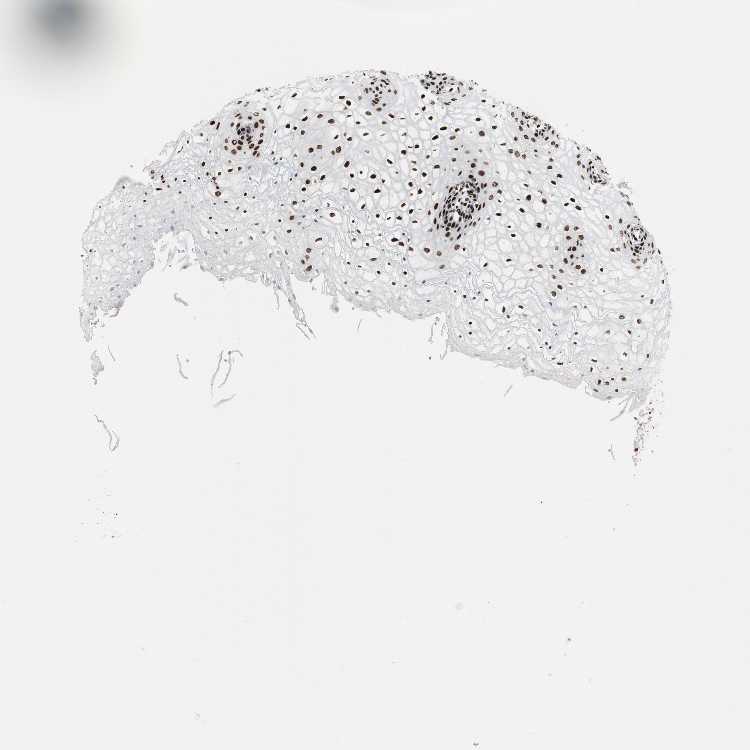

VAGINA - Antibody stainingi

Antibody staining in the annotated cell types in the current human tissue is reported as not detected, low, medium, or high, based on conventional immunohistochemistry profiling in selected tissues. This score is based on the combination of the staining intensity and fraction of stained cells.

Each image is clickable and will lead to virtual microscopy that enables deeper exploration of all samples and also displays staining intensity scores, fraction scores and subcellular localization as well as patient and tissue information for each sample.

Antibody HPA006214Antibody CAB005315Antibody CAB017522

Squamous epithelial cells HighHighHigh